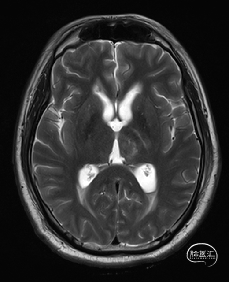

术前DTI检查

根据MRI及DTI显示,只有在丘脑与上丘之间的点(dot)进入病变才可能在切除病变时最大程度保护神经功能,由于上述原因,该“点”在术中显露极其困难,虽有导航指引,电生理监测的条件下,对术者的耐心、技术、经验及体能依然是极大的挑战;

术前详细的磁共振检查,包括平扫增强,SWI及DTI,可以规划出手术最适宜的路径及切入点;